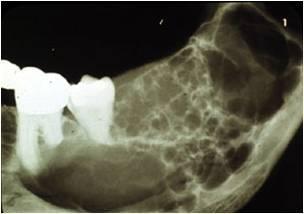

Рентгенологическая диагностика саркомы у кошек

Раздел: Визуальный дайджест